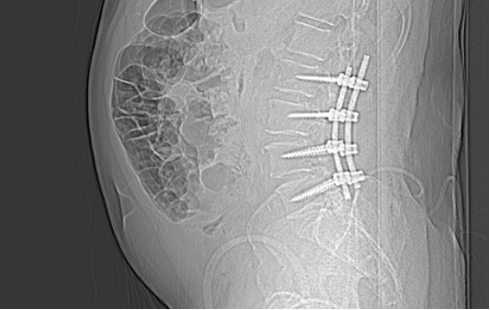

Üç yıl kadar önceki bu muayene ve tetkikler sonucunda Akın Bey, bana “henüz ameliyat safhasında değilsiniz, biraz daha fizik tedavi ve ağrı kesicilerle devam edelim” demişti. O günkü radyolojik tetkiklerde L4-L5 bölgesinde “lomber spinal stenoz” tabir edilen kanal daralmasından bahsediliyordu aslında. Bunun lomber dar kanal (spinal stenoz) ve buna eşlik eden spondilolistezis olduğu ifade edildi. Ben anlatması kolay olsun diye sinirlerin geçtiği omurga kanallarının daralması diyorum.

Ameliyatın bazı safhalarının video kaydını seyrettim daha sonra. Ne kadar hassas ve ince bir işlem olduğunu bir kere daha müşahede etmiş oldum. Omurgada milimetrenin küsurları bile önem kazanıyor. Oraya metallerin yerleştirilmesi büyük bir hassasiyet gerektiriyor. Akın Hoca bana ‘iğne ile kuyu kazmaya benzer bizim omurga üzerindeki işlemlerimiz’ demişti. O bakımdan doktorlar az da olsa bir endişe içinde ameliyatı sona erdiriyorlar ama ilk fırsatta bu metallerin yerli yerinde olup olmadığını ve omurga kanallarındaki daralmanın giderilip giderilmediğini görmek istiyorlar. Bu sebeple beni sabah saat 05.30’da gelip tomografiye götürdüler ve ortaya çıkan neticeyi görmek istediler. Daha sonra odama gelen Dr. Akın Bey ve arkadaşları yerleştirilen metal parçacıklarının tam istedikleri konumda olduğunu gördüklerini söylediler ve beni rahatlattılar. Şu anda omurgamda dört adet bir tarafta, dört adet diğer tarafta olmak üzere sekiz metal parçası taşıyorum. Yani omurgama yerleştirilen vidalar ve sabitleyici metal çubuklarla geziyorum.

Ameliyatın üzerinden iki buçuk ay geçtikten sonra Dr Akın Hocaya gittim kontrol için. Yeniden tomografi çekildi. Hoca, her şey yolunda dedi ama beni kemik erimesi kaygısıyla başka bir uzmana yönlendirdi. ‘Bu bir tedbirdir’ diye de vurguladı. Şimdi onun neticelerine de bakarak korseyi daha ne kadar taşımam gerektiğine karar verecek.